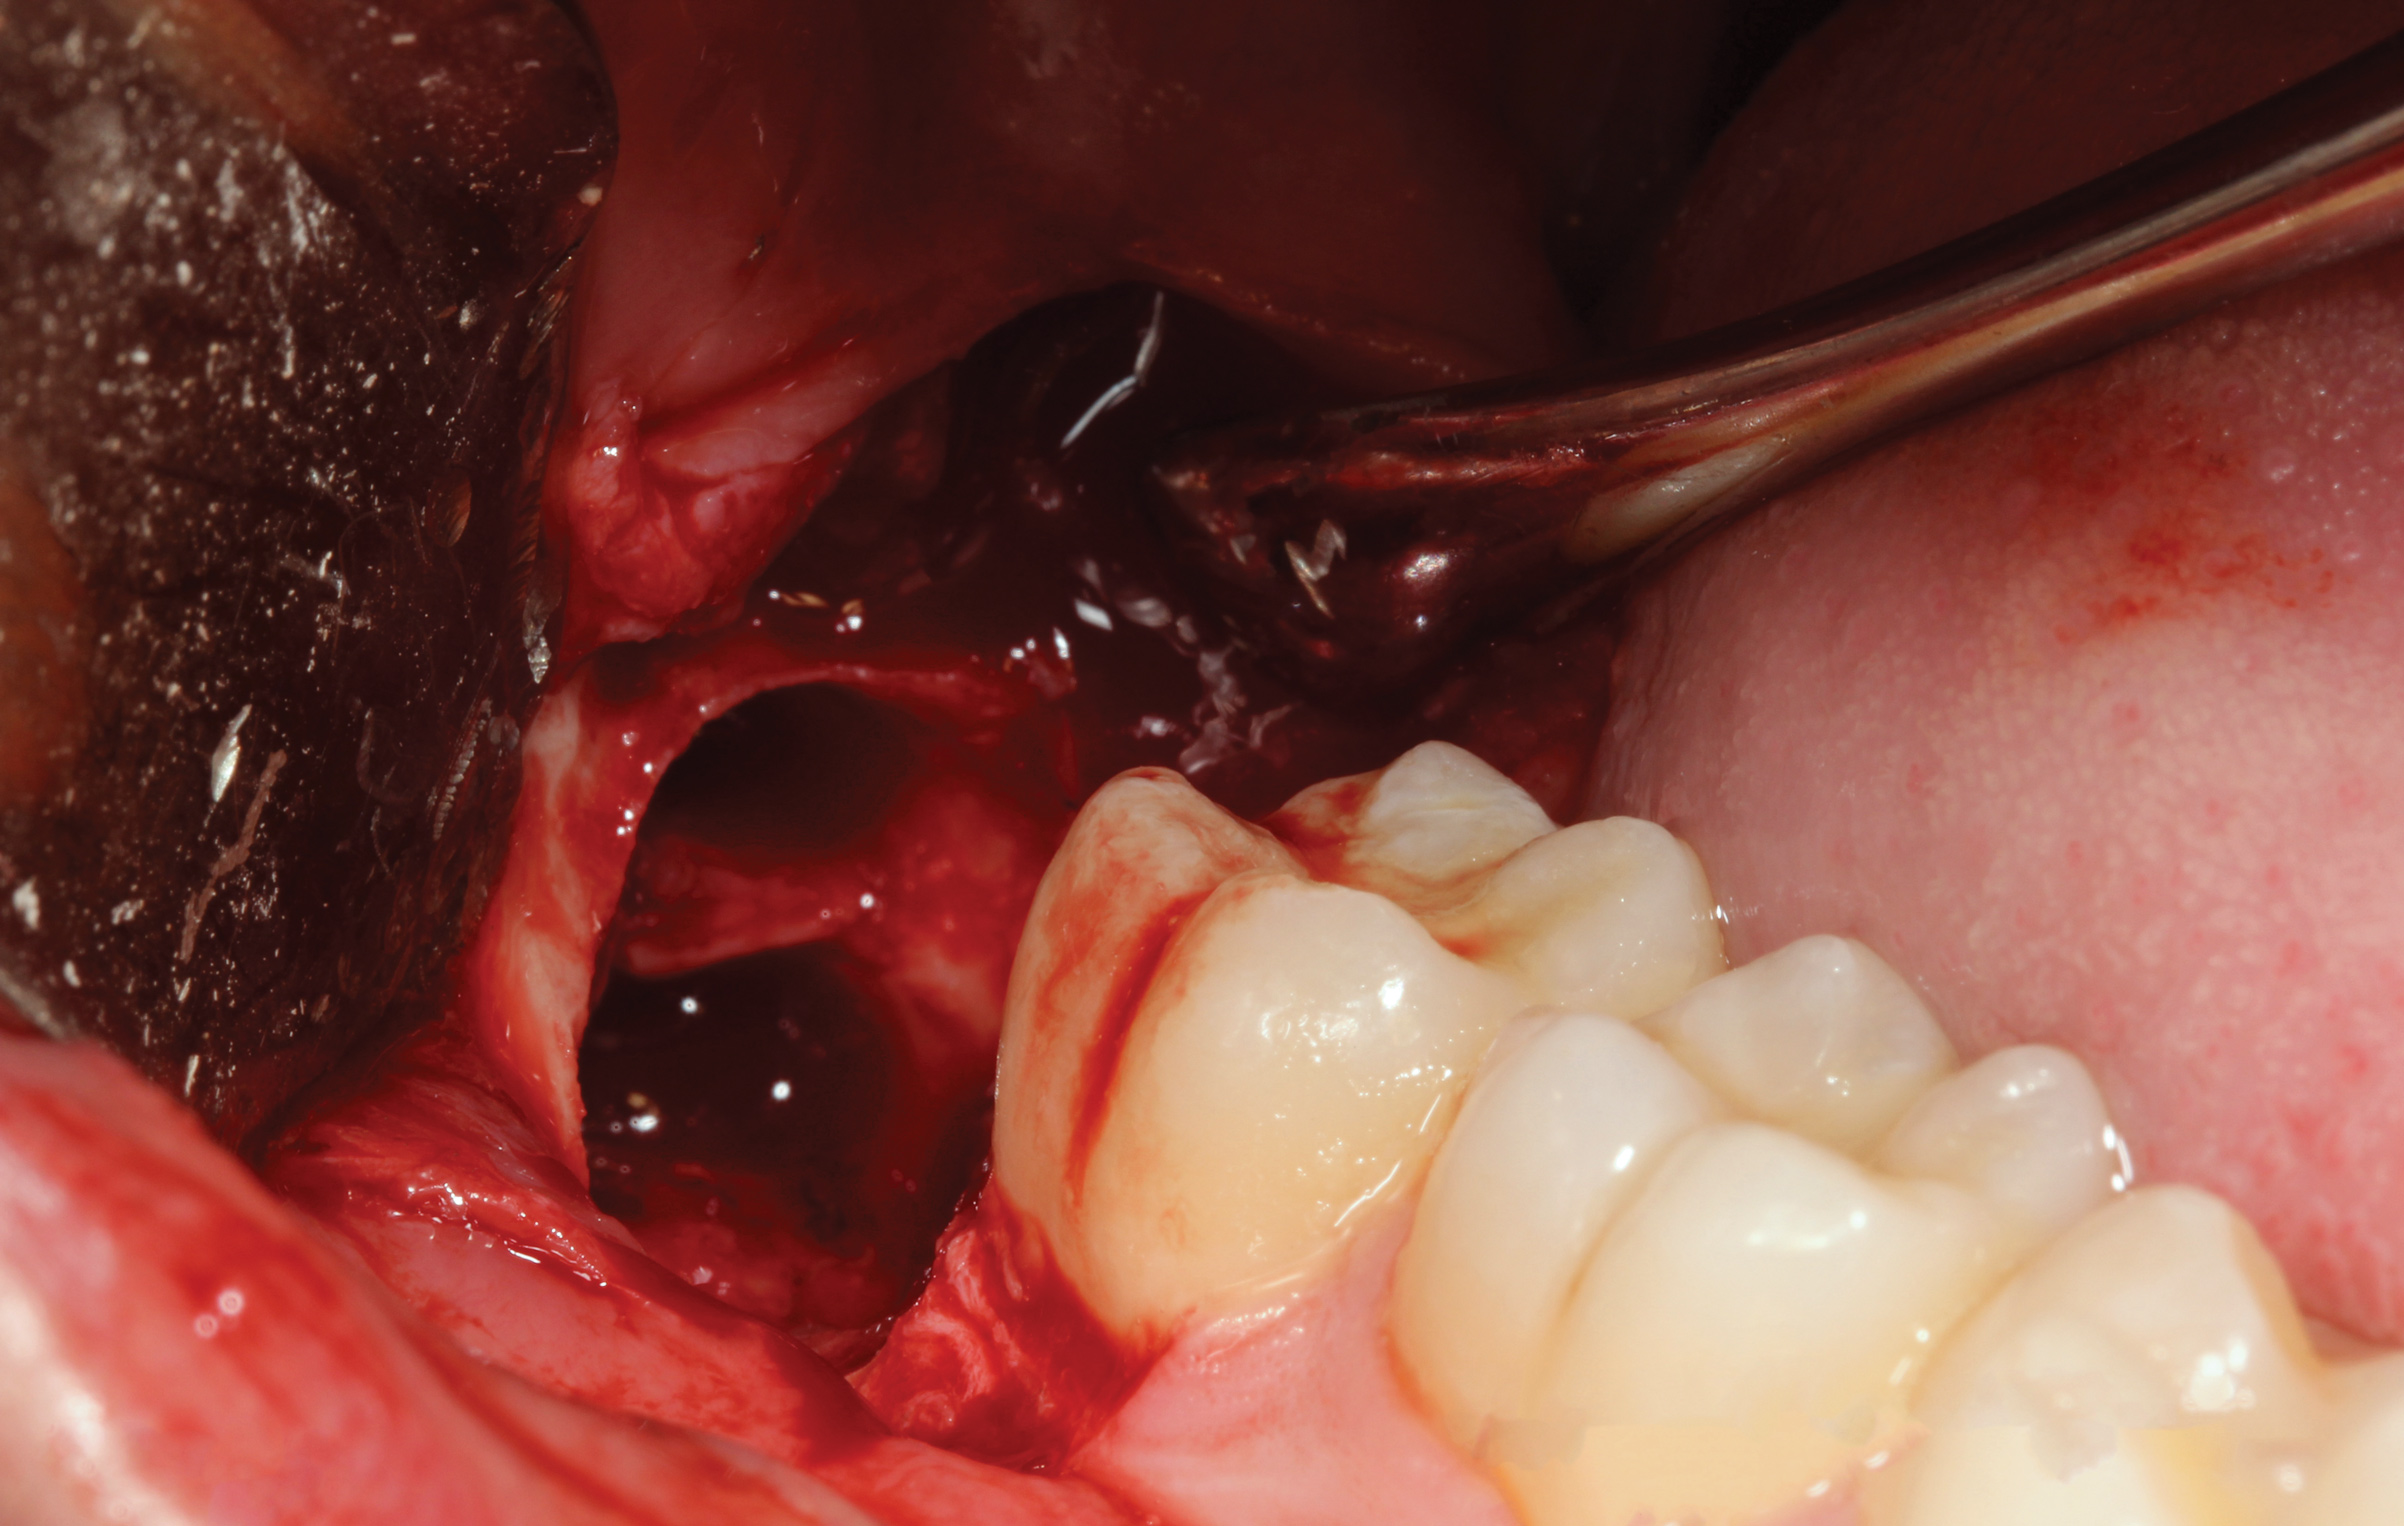

Fig 3. Extraction socket after removal of the impacted mandibular third molar.

Figure 3

A presurgical rinse of 0.2% chlorhexidine (CHX) solution was performed, followed by administration of local anesthetic using 4% articaine with epinephrine solution. A crestal incision with a vertical releasing incision at the mesial aspect of the surgical area was made, and a full-thickness mucoperiosteal flap was elevated (Figure 1). A buccal and, if required, distal osteotomy was performed using a round carbide bur on a straight handpiece. When necessary the tooth was dissected to allow it to be elevated and extracted (Figure 2). When performing the third molar extraction care was taken to not damage the adjacent second molar tooth nor its supporting alveolar bone. The extraction socket was thoroughly debrided with hand instruments and rinsed with a 0.2% CHX solution to decrease bacteria in the socket (Figure 3).35